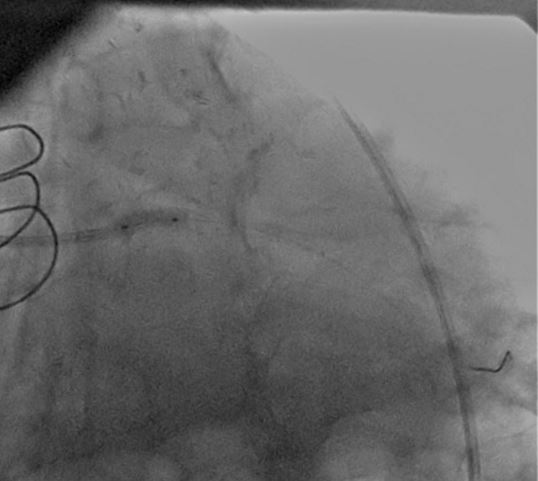

A CLs guiding catheter was used to engage the left coronary artery, and a Choicd floppy guidewire passed through the lesion. The lesion was predilated with a 1.5x15mm and 2x10mm Maveric balloon (figure 4). Then a 3.5x18mm Xience v stent was deployed at 16atm (figure 5, figure 6, figure 7). Post-dilation was done with a 4x10mm Firestar NC balloon (figure 8). The final result showed TIMI-III flow with no residual stenosis (figure 9).